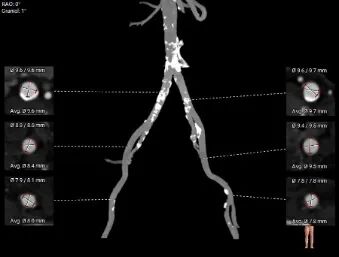

双侧股动脉入路条件尚可,钙化分布较多,以右侧股动脉为主入路,TaurusElite输送器柔顺性好通过性佳,可较为安全的完成植入。

入路评估